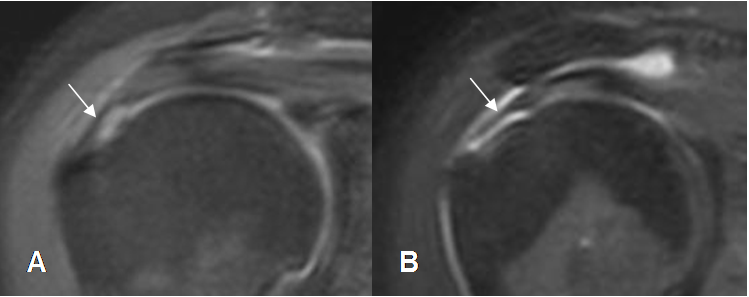

Fig 116. Ruptura parcial del supraespinoso.

A: RM coronal en T2 y B: RM coronal en STIR. Ruptura parcial del tendón supraespinoso hacia la superficie humeral (Flechas delgadas), con fibras íntegras en la superficie bursal. (Flechas gruesas).